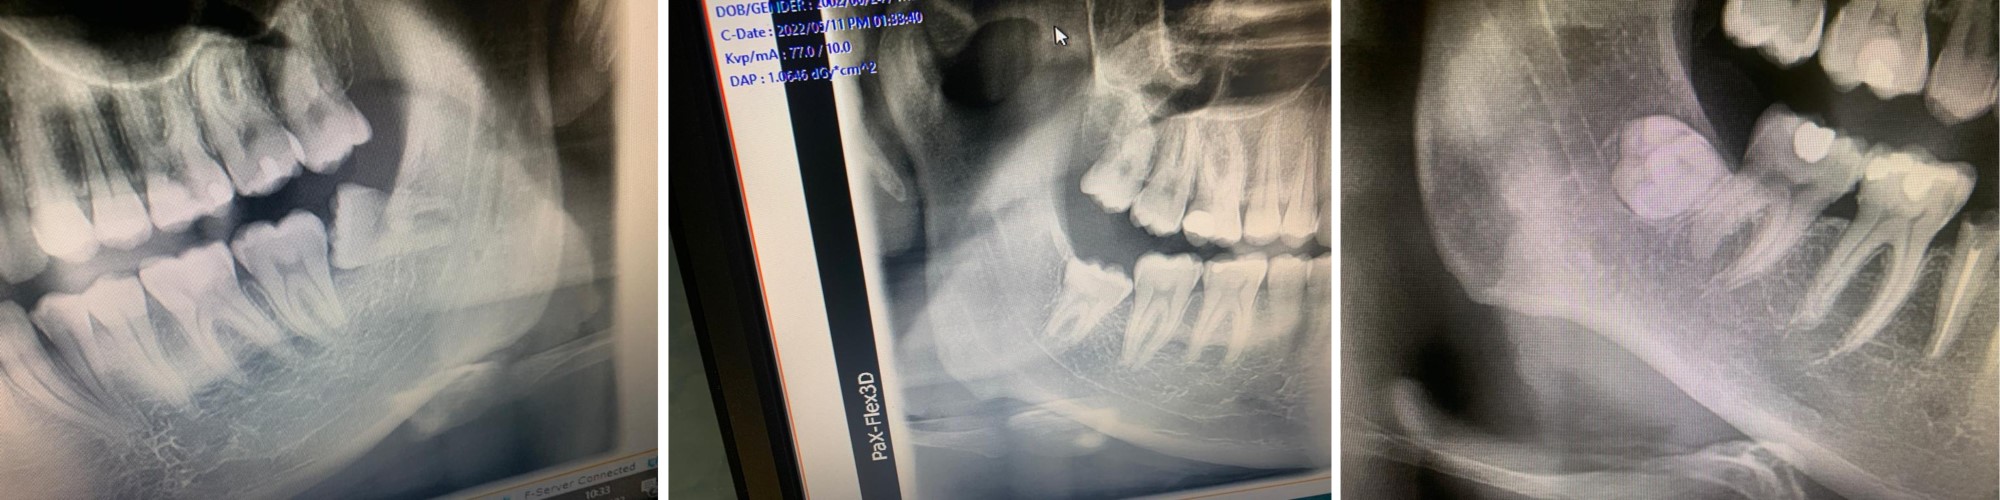

Alcuni esempi di denti del giudizio inclusi o in disodontiasi rimossi chirurgicamente